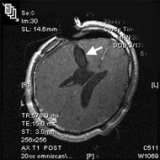

Pre Operative RMI Ependymoma

A pre-operative MRI image (above) shows an ependymoma (arrow) in the right lateral ventricle.